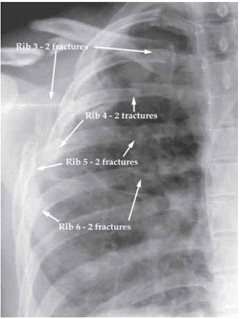

האבחנה של Flail chest היא קלינית ורנטגנית. בצילום חזה, ניתן לראות שברים בשני מקומות באותה הצלע במספר צלעות (תצלום 9.16). ב-CT חזה ניתן לראות תמונה דומה.